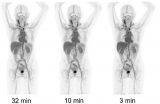

对于肿瘤免疫治疗的在体可视化显像监测,最初采用的方法是在过继性细胞免疫疗法(Adaptive Cell Therapy,ACT)中使用放射性示踪剂直接标记免疫细胞,将标记好的免疫细胞回输到患者体内,进行核素显像示踪细胞。

2022-10-28

PET/CT